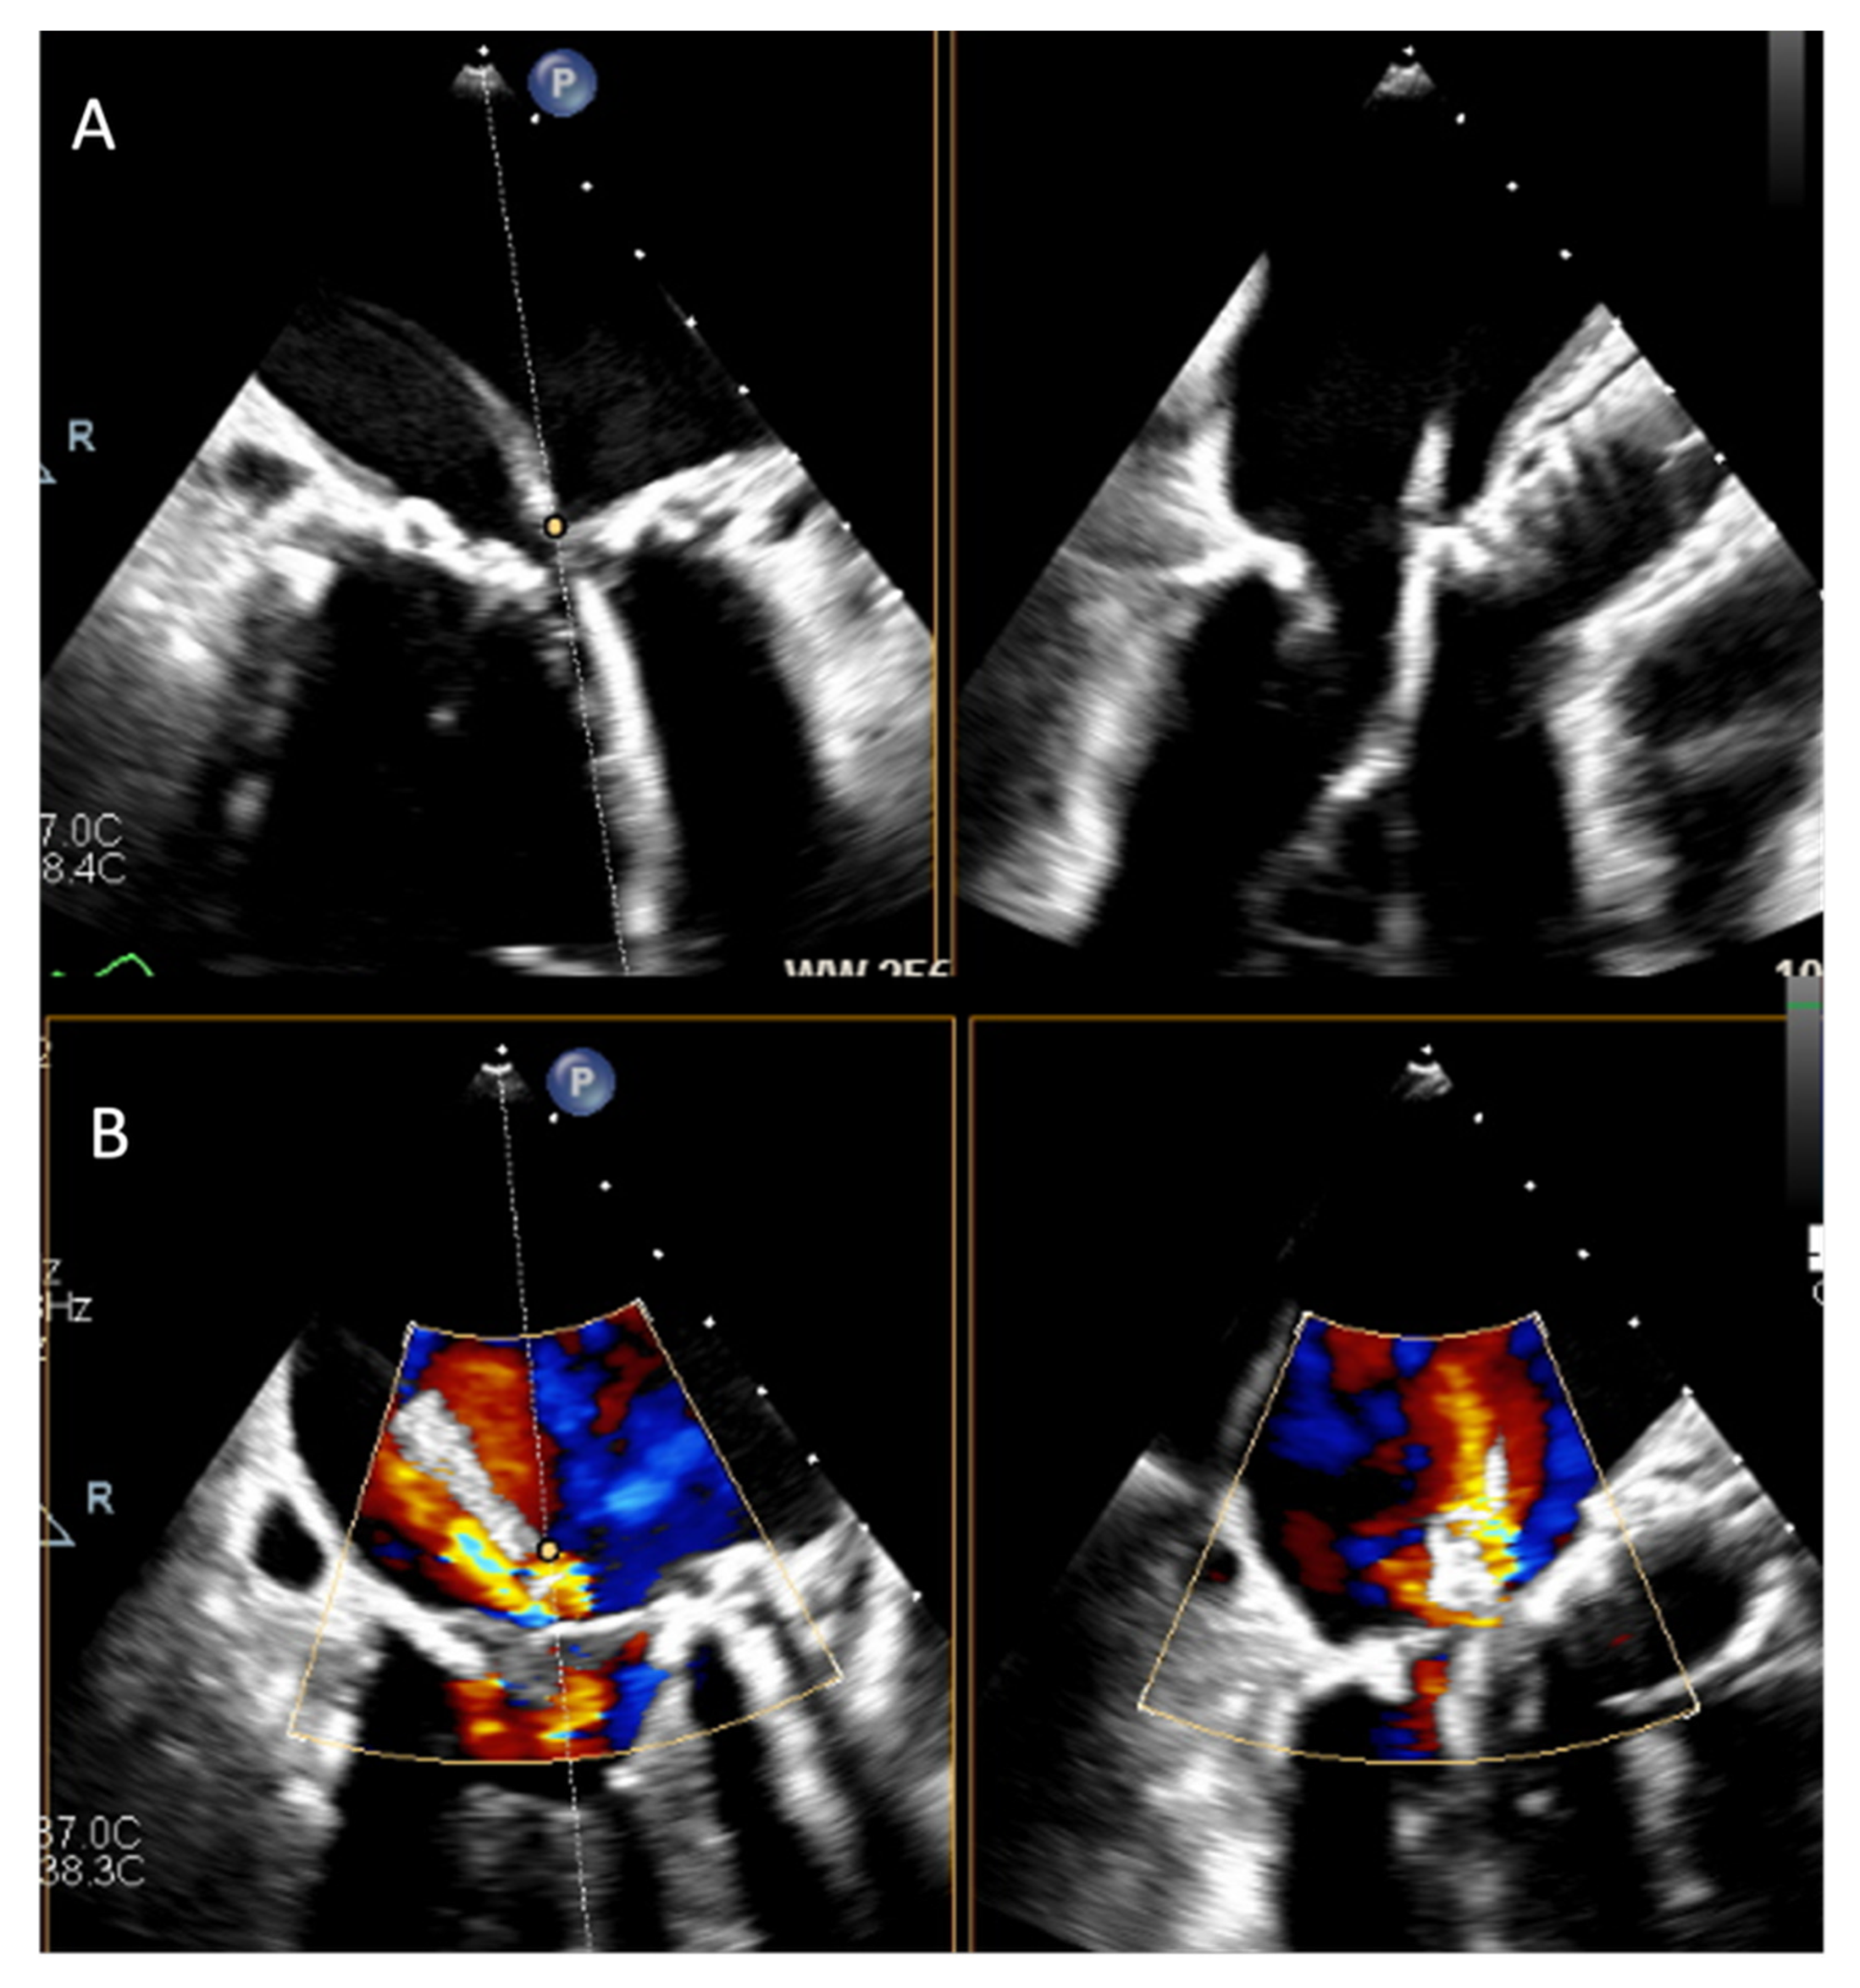

3.3. Calcification and Sealing

3.4. Confirmation of Positioning

3.5. Post-Deployment Assessment

5.1. Valve-in-Valve, Valve-in-Ring, and Annuloplasty

5.2. Valve-in-MAC (ViMAC)